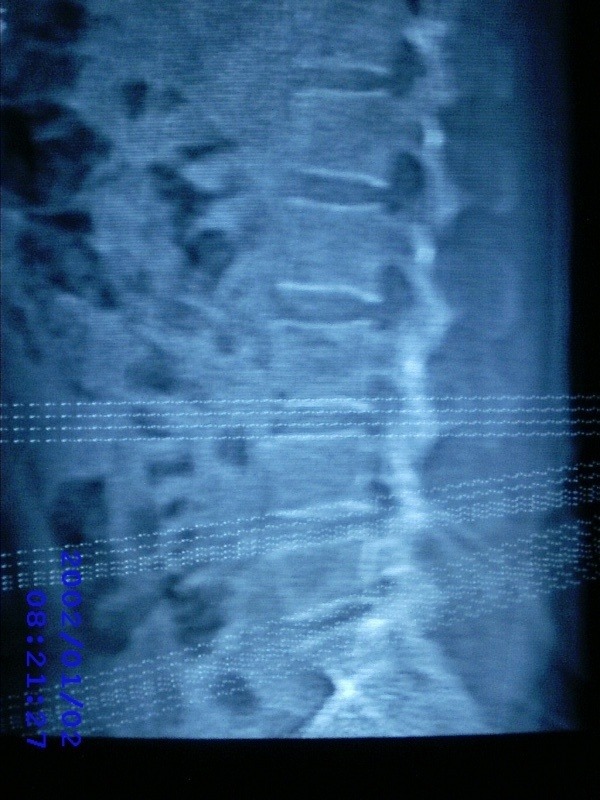

患者,男性,40岁,腰痛伴左下肢疼痛、麻木6年。5年前做过腰椎间盘手术,具体是哪个位置病人记不清了。

我拍的是l4-5、l5-s1

1)l4/5及l5/s1左侧椎板术后改变。2)l5/s1椎间盘突出,l5椎体下缘许莫氏结节。3)l4/5椎间盘膨出并突出。4)l3/4椎间盘膨出。